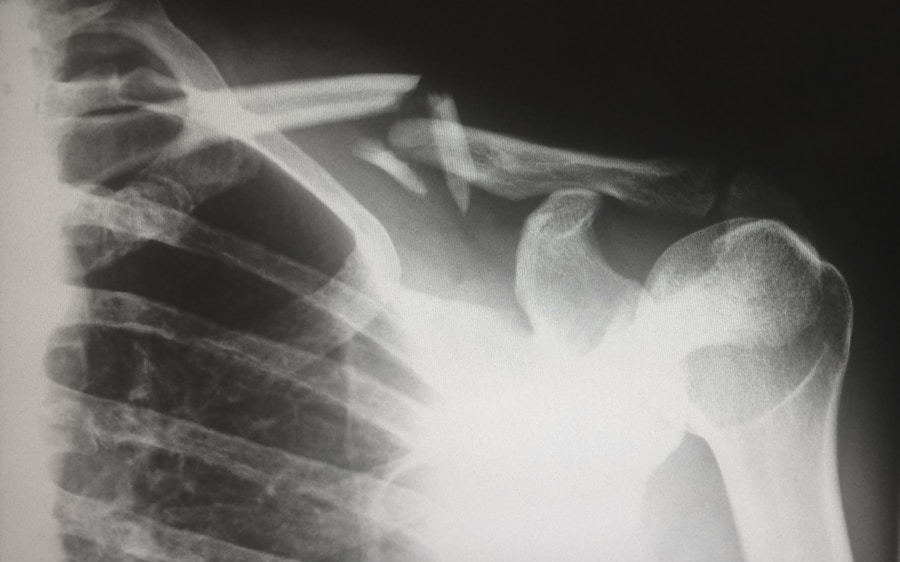

La radiologia ci permette di “vedere” all’interno delle articolazioni, come se avessimo dei raggi X.

- Radiografia (RX): È spesso il primo esame strumentale richiesto per valutare lo stato delle ossa e delle articolazioni. Può mostrare alterazioni ossee, restringimento dello spazio articolare, osteofiti (speroni ossei) tipici dell’osteoartrosi, o erosioni caratteristiche di alcune forme di artrite. È un po’ come scattare una foto dello scheletro.